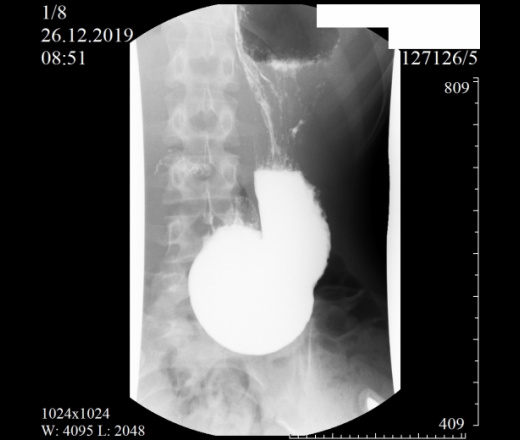

Девочка, 2004 г. Направлена с диагнозом ФНГ печени в онкоцентр. Приложены снимки рентгеноскопии ЖКТ. Помогите с интерпретацией, очень редко с этим работаем. Спасибо.

Как понимать аббревиатуру ФНГ? Не брался бы выность заключение после проведения Rg-скопии желудка, только по представленным снимкам. Можно однозначно сказать, что есть гипотония желудка( некотрые врачи используют термин гастроптоз).

PS С учетом избытка желудочного содержимого (впечатление, что в просвете не только жидкость, но и слизь), вялой перистальтики, можно подумть о хроническом гастрите. Не видя исследования вживую, всё только догадки.

"(красиво начали, жаль, оборвали) - гипотонус желудка, гипотонус луковицы ДПК, вероятный дуодено-гастральный рефлюкс, аорто-мезентериальная компрессия ДПК (стадия 1 или 2, не скажу - недостаточно снимков, скопию закончили рано), птоз тощей кишки и колоноптоз. "©